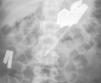

Ingesta de cuerpos muy extraños

Intake of very foreign bodies